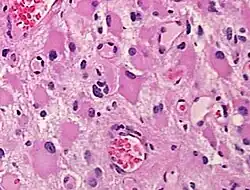

A gemistocyte (/dʒɛˈmɪstəsaɪt/ jem-ISS-tə-syte; from Greek γέμιζω (gemizo) 'to fill up') is a swollen, reactive astrocyte.

Gemistocytes are glial cells that are characterized by billowing, eosinophilic cytoplasm and a peripherally positioned, flattened nucleus. Gemistocytes most often appear during acute injury; and eventually, shrink in size.[1] They are usually present in anoxic-ischemic brains, which occurs when there is a complete lack of blood flow to the brain. Anoxic-ischemic brains usually occur in patients who have had cardiac arrest and prolonged attempt at cardiopulmonary resuscitation.[2]

When present in anoxic-ischemic brains, gemistocytes are regularly encountered in glial neoplasms, also known as glioma, which is a type of tumor that occurs in the brain and spinal cord. Usually, gliomas begin in the glial cells that surround the nerve cells to help them function. Many gliomas exhibit cells that do not exist in normal brain tissue and are not seen in glial differentiation.[1] Of these gliomas are astrocytomas, which is a type of cancer that occurs in the brain or spinal cord. The main role of astrocytes is to maintain brain homeostasis and neuronal metabolism. When the astrocytes become activated, they begin to respond to damage.[3] Astrocyte activation, known as astrogliosis, responds to neurological trauma, infections, degradations, epilepsy, and tumorigenesis. Each neurological insult plays a major role in astrocyte activation and response to that specific damage. In some astrocytomas, the number of gemistocytes is extremely overwhelming, terming it a “gemistocytic astrocytoma.” Not only are gemistocytic cells present in astrocytomas, but they are also found in various glial tumor cells; for example, oligodendrogliomas, mixed oligoastrocytomas, glioblastomas, and pleomorphic xanthoastrocytomas. Gemistocytes are known to have a large cytoplasmic mass, long, branching processes, and increased cytoplasmic filaments.[1] The cytoplasm of gemistocytes stains positive for glial fibrillary acidic protein, GFAP. While the intermediate filaments in gemistocytes are diffused throughout the cytoplasm, which indicates cellular disintegration. Within these different tumor types, the term “mini-germistocytes” is used for smaller gemistocytes, that are usually found in oligodendroglial tumors. Mini-germistocytes are found to have a very ordered arrangement of filaments throughout the cytoplasm, but may also transform into the end-state morphology of the larger gemsitocytic cells. Studies have suggested that both classic gemistocytes and mini-gemistocytes show similar genetic variation to non-gemistocytic tumor cells.[4] Mini-germistocytes, usually found in oligodendroglial tumor cells, express gliofibrillary oligodendrocytes, or GFOCs, which are capable of transforming the mini-gemistoctyes into larger gemistocytes.